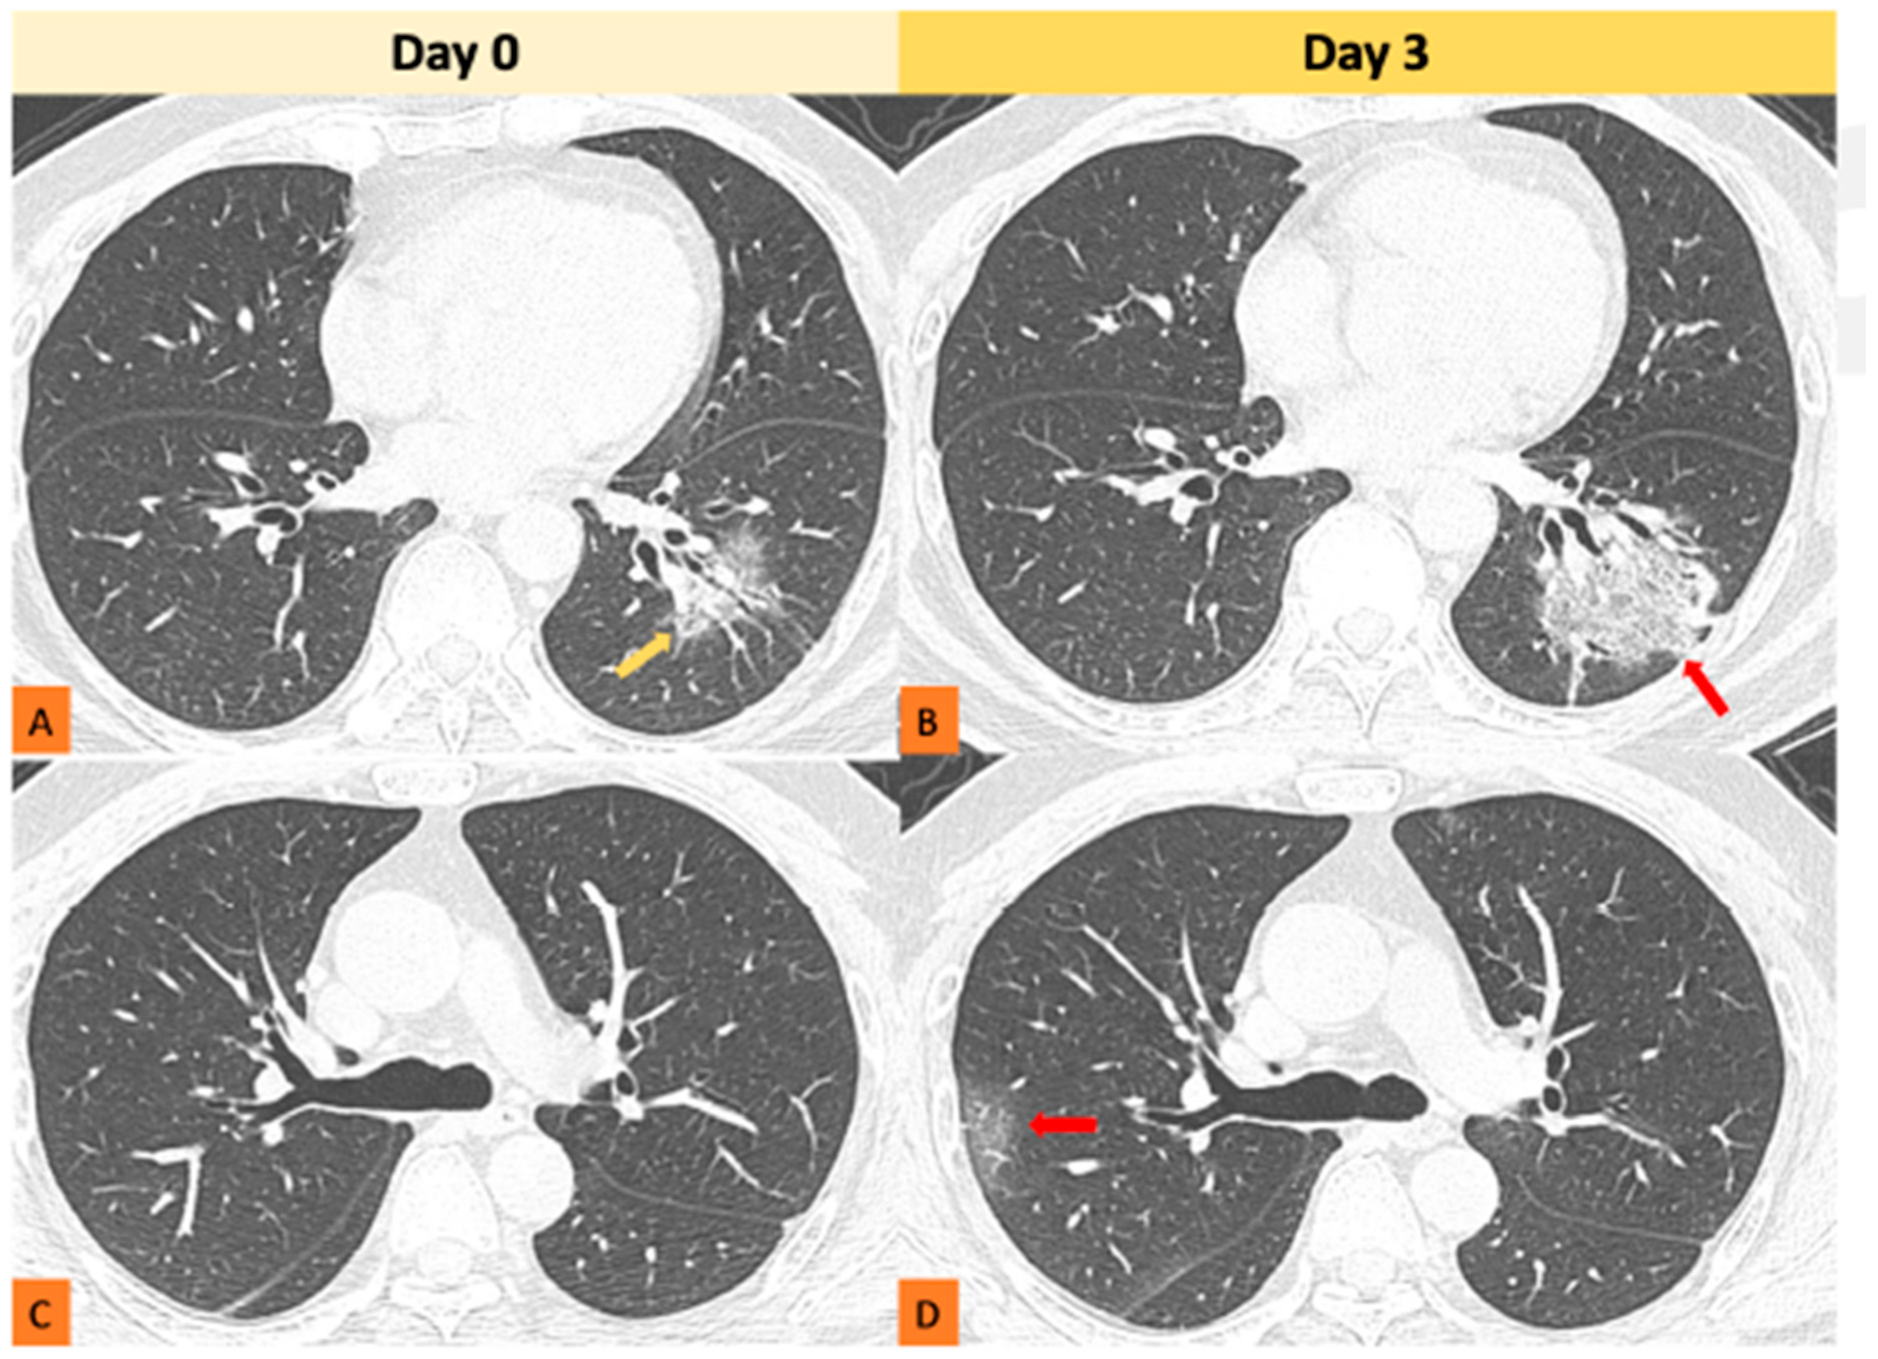

- Kang, D.H.; Kim, G.H.J.; Park, S.-B.; Lee, S.-I.; Koh, J.S.; Brown, M.S.; Abtin, F.; McNitt-Gray, M.F.; Goldin, J.G.; Lee, J.S. Quantitative Computed Tomography Lung COVID Scores with Laboratory Markers: Utilization to Predict Rapid Progression and Monitor Longitudinal Changes in Patients with Coronavirus 2019 (COVID-19) Pneumonia. Biomedicines 2024, 12, 120. [Google Scholar] [CrossRef]

- Mousa, M.; Matar, M.; Matar, M.; Jaber, S.; Jaber, F.S.; Al Ajerami, Y.; Falak, A.; Abujazar, M.; Oglat, A.A.; Abu-Odah, H. Role of cardiovascular computed tomography parameters and lungs findings in predicting severe COVID-19 patients: A single-centre retrospective study. Egypt. J. Radiol. Nucl. Med. 2022, 53, 1–11. [Google Scholar] [CrossRef]

- Oglat, A.A.; Oqlat, M.A.; Oqlat, A.A.; Alanagreh, L.A.; Khaniabadi, P.M.; Dheyab, M.A.; Khaleel, H.; Althalji, O. Imaging Aspects (Chest Radiographic and CT Scan Findings) of COVID-19 with Clinical Classifications. Jordan J. Biol. Sci. 2022, 15. [Google Scholar]